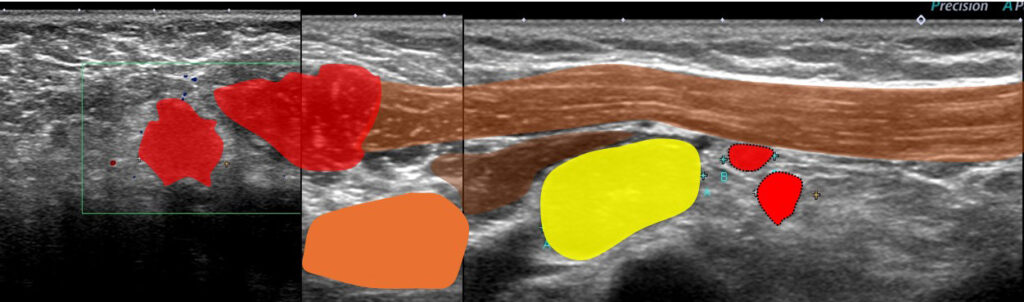

これらエコーをつなぎ合わせたもの

リンパ節は黄色に表現

大胸筋(茶色)の裏に小胸筋(こげ茶色)

大胸筋の外側にリンパ節2つ、大胸筋の裏にリンパ節1個 これら3個がレベルⅠ

小胸筋裏にリンパ節(これが最大で2㎝)これがレベルⅡ

それより内側(奥)に比較的小さいリンパ節2個 これらがレベルⅢ

色分けすると 赤とオレンジ:レベルⅠ、 黄色:レベルⅡ 、赤(周囲に点線の小さいもの):レベルⅢ